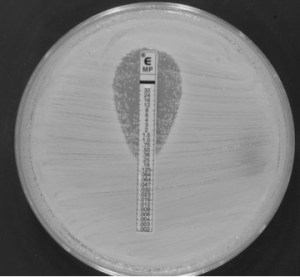

- Medicina personalizada de precisión (MPP) en enfermedades infecciosas: explotemos el antibiograma